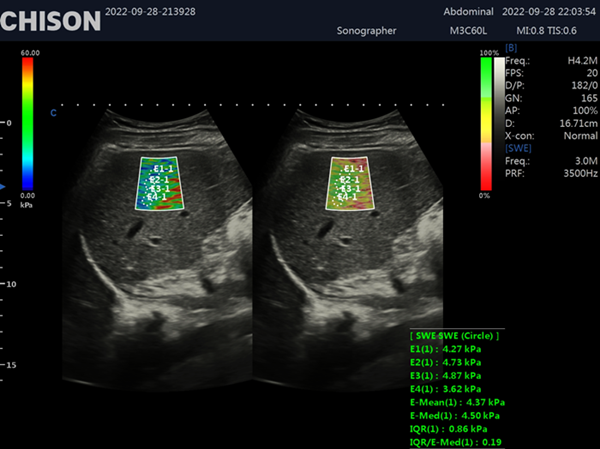

Shear wave elastography is a non-invasive imaging technique that measures tissue stiffness by generating and analyzing shear waves within the body. By utilizing ultrasound technology, shear wave elastography offers a unique perspective into the mechanical properties of tissues, enabling healthcare professionals to diagnose a wide range of conditions accurately.

Shear wave elastography relies on the propagation of shear waves through tissues. These waves are generated by the application of acoustic radiation force, which causes displacements within the tissue. By measuring the speed at which these waves travel, shear wave elastography can determine the elasticity and stiffness of tissues. This information is then visualized using color maps, providing clinicians with valuable diagnostic information.

One of the most notable applications of shear wave elastography is in the assessment of liver disease. Traditional methods, such as liver biopsy, are invasive and carry certain risks. However, shear wave elastography provides a non-invasive alternative that can accurately quantify liver stiffness, aiding in the diagnosis and monitoring of conditions such as fibrosis and cirrhosis.

Shear wave elastography represents a significant advancement in the field of diagnostic imaging. With its ability to assess tissue stiffness non-invasively and provide valuable diagnostic information, this technique has revolutionized medical imaging across various specialties. From liver disease assessment to breast lesion characterization and musculoskeletal evaluations, shear wave elastography continues to enhance our understanding and management of numerous conditions. XBit 90 has both P-SWE point shear wave imaging and 2D-SWE surface shear wave imaging. Provide a variety of quantitative analysis parameters, such as velocity values, Young's modulus, and so on. Embracing this cutting-edge technology can empower healthcare professionals to deliver superior patient care and make more informed clinical decisions.